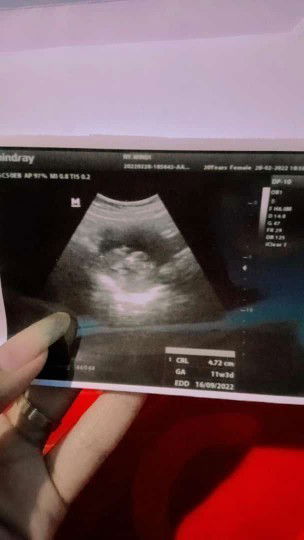

Alhamdulillah baru pertama kali USG si dedek udh kelihatan,pernah ngeflek gara2 kecapean si dedek tumbuh sehat,di usg usia kandungan baru 11minggu 3 hari di perhitungan bidan udah 12 minggu😂itu normal ngk sih bun sempat worry bgt kok bisa beda yg hplnya 12 September jadi 16 September #seriusnanya #bantusharing